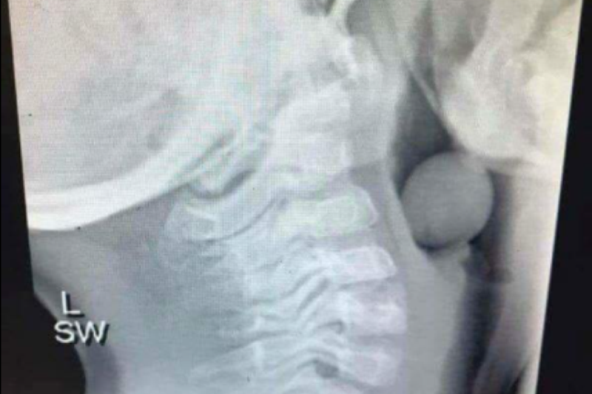

Internetom se ponovno širi fotografija rendgenskog snimka petogodišnjeg deteta. Naime, na njoj se jasno vidi kako se bobica grožđa zaglavila detetu u disajnim putevima.

"Bila je potrebna operacija da bi se bobica grožđa uklonila, a budući da nije potpuno blokirala disajni put, dete je preživelo. Grožđe treba prepoloviti deci kako bi se izbegle posledice. Ovo se dogodilo petogodišnjem detetu. Ljudi, secite grožđe", opis je fotografije koju je podelio korisnik Fejsbuka Tod Džensi još 2019. godine, a koja je do danas podeljena skoro 650.000 puta.